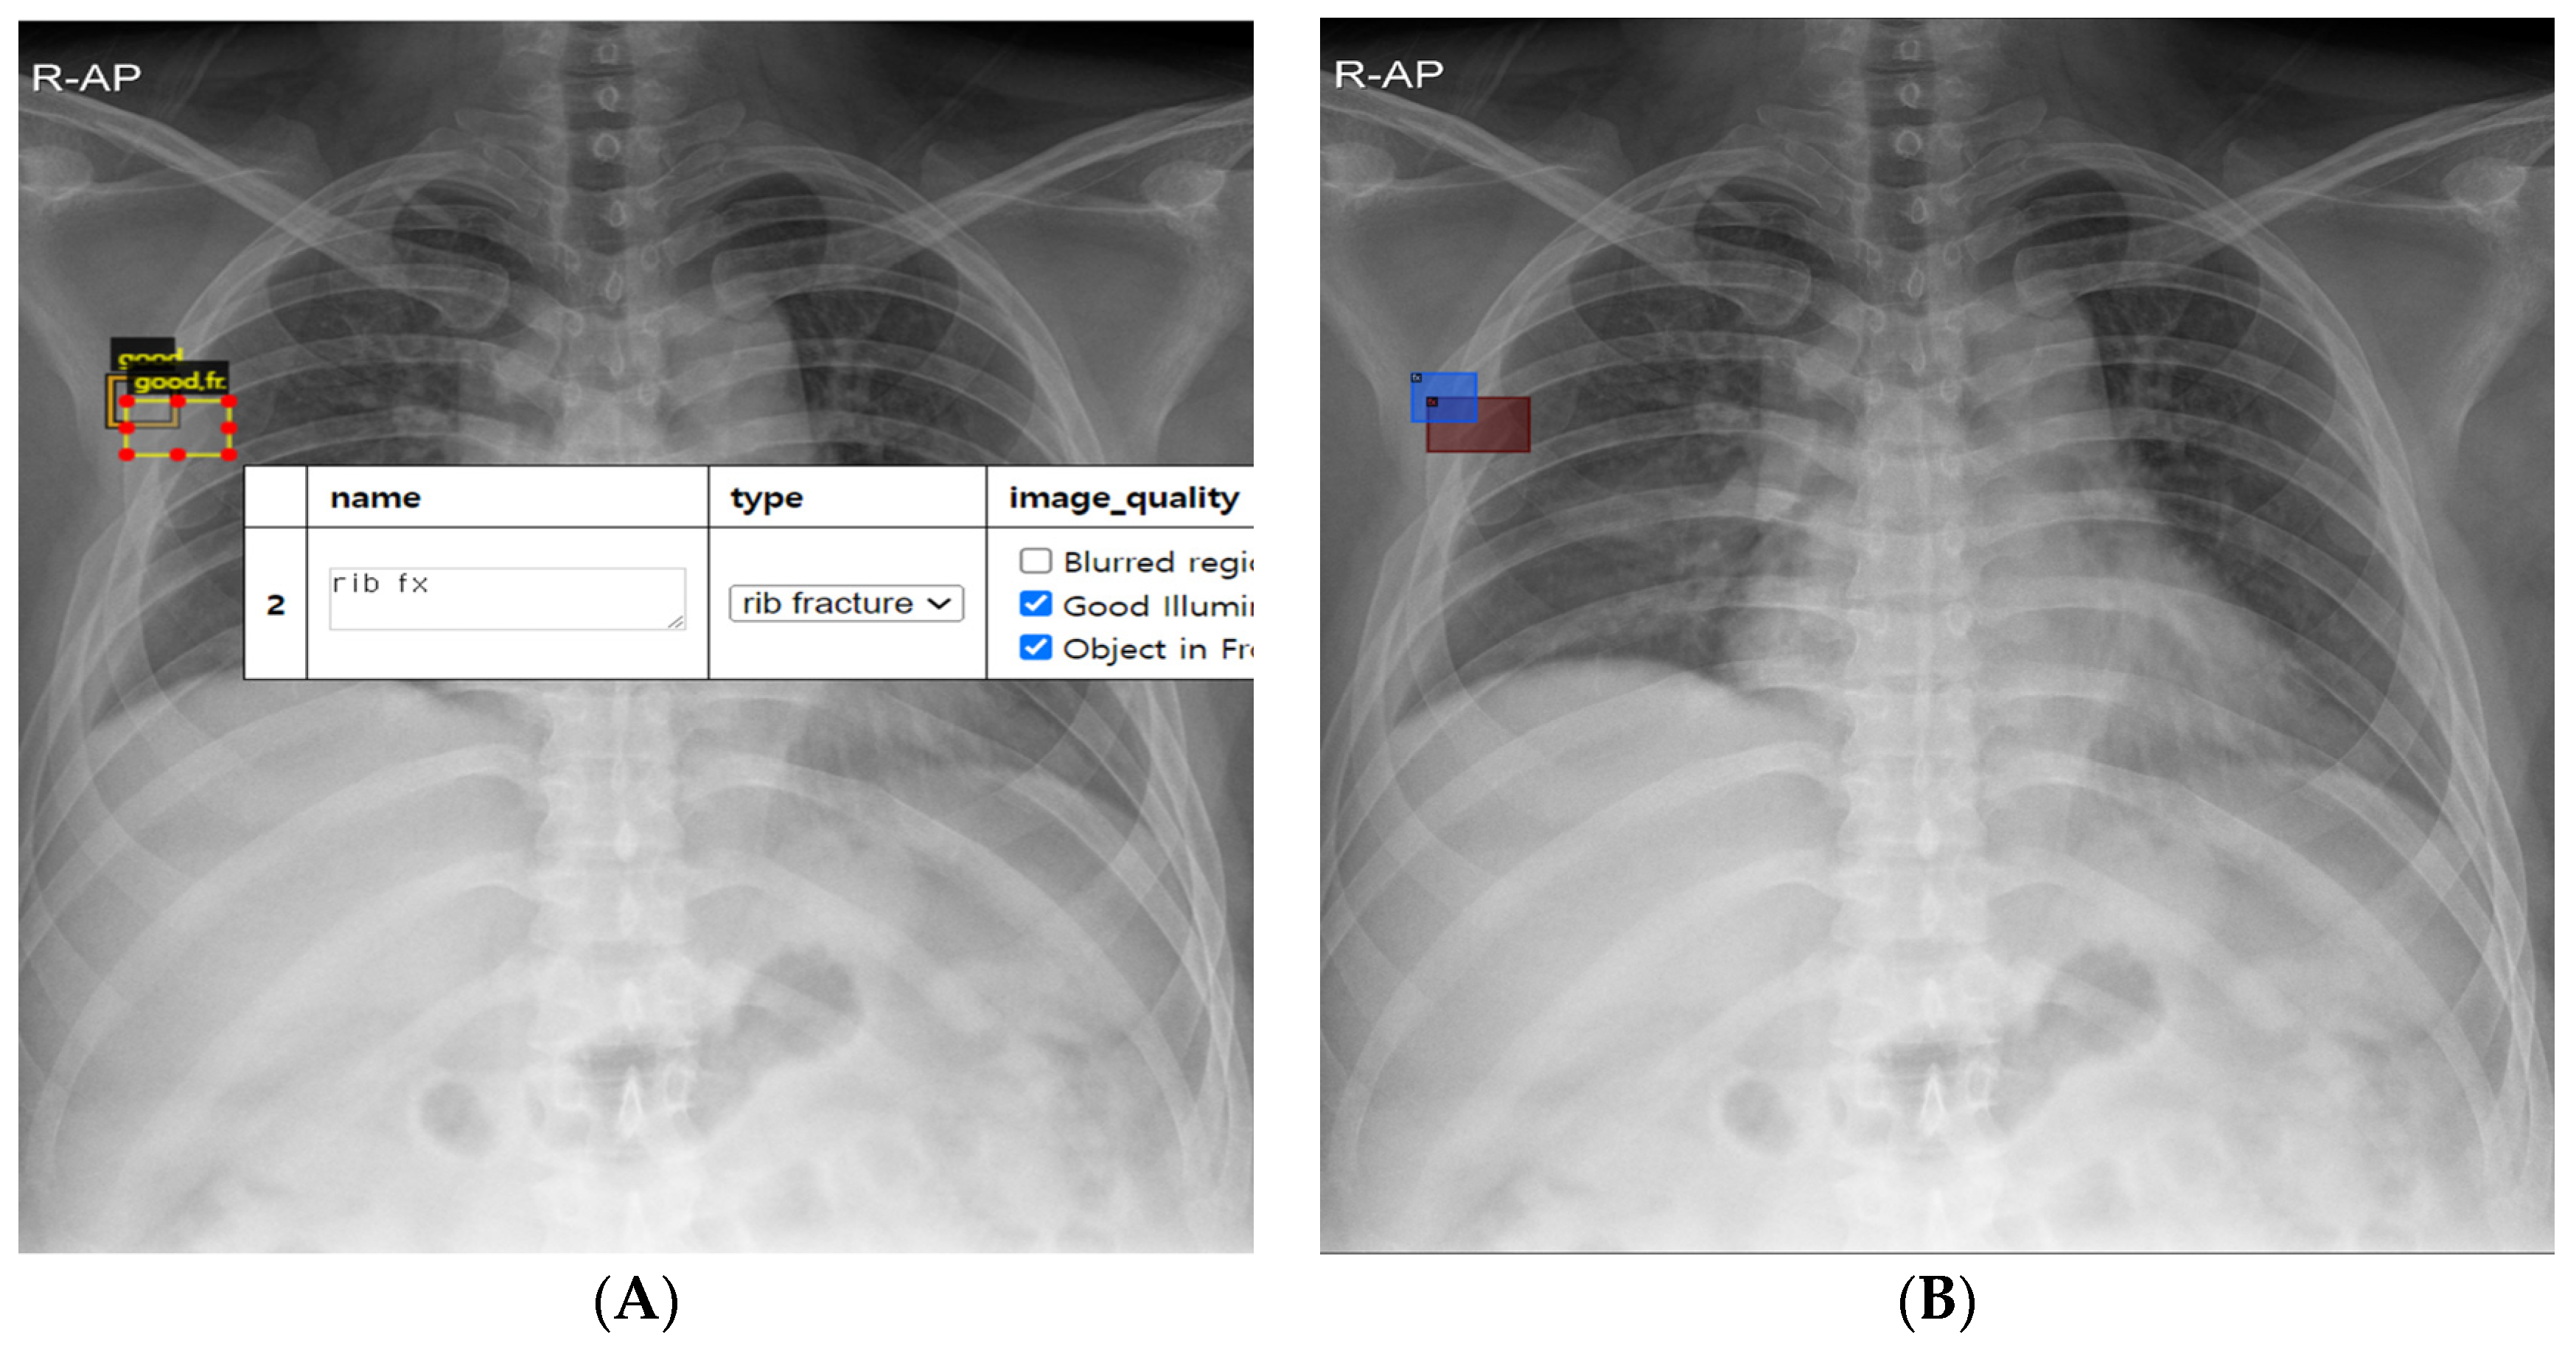

2.2. Rib Fracture Annotation on Chest Radiographs